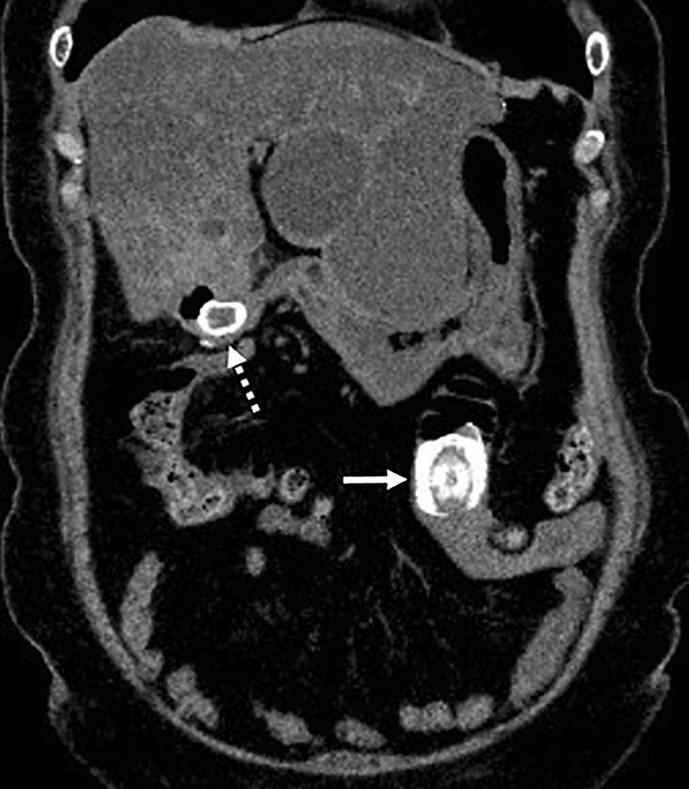

Case presentation: A 69-year-old female presented to the emergency department with nausea, emesis, and abdominal pain. After computed tomography revealed the diagnosis of gallstone ileus, enterolithotomy was performed without postoperative complications. Cholecystectomy and fistula closure were not performed due to inaccessibility to the gallbladder and the high surgical invasion required. Four months later, the patient developed gallstone ileus again. A second enterolithotomy was performed immediately, resulting in a favorable outcome without complications.